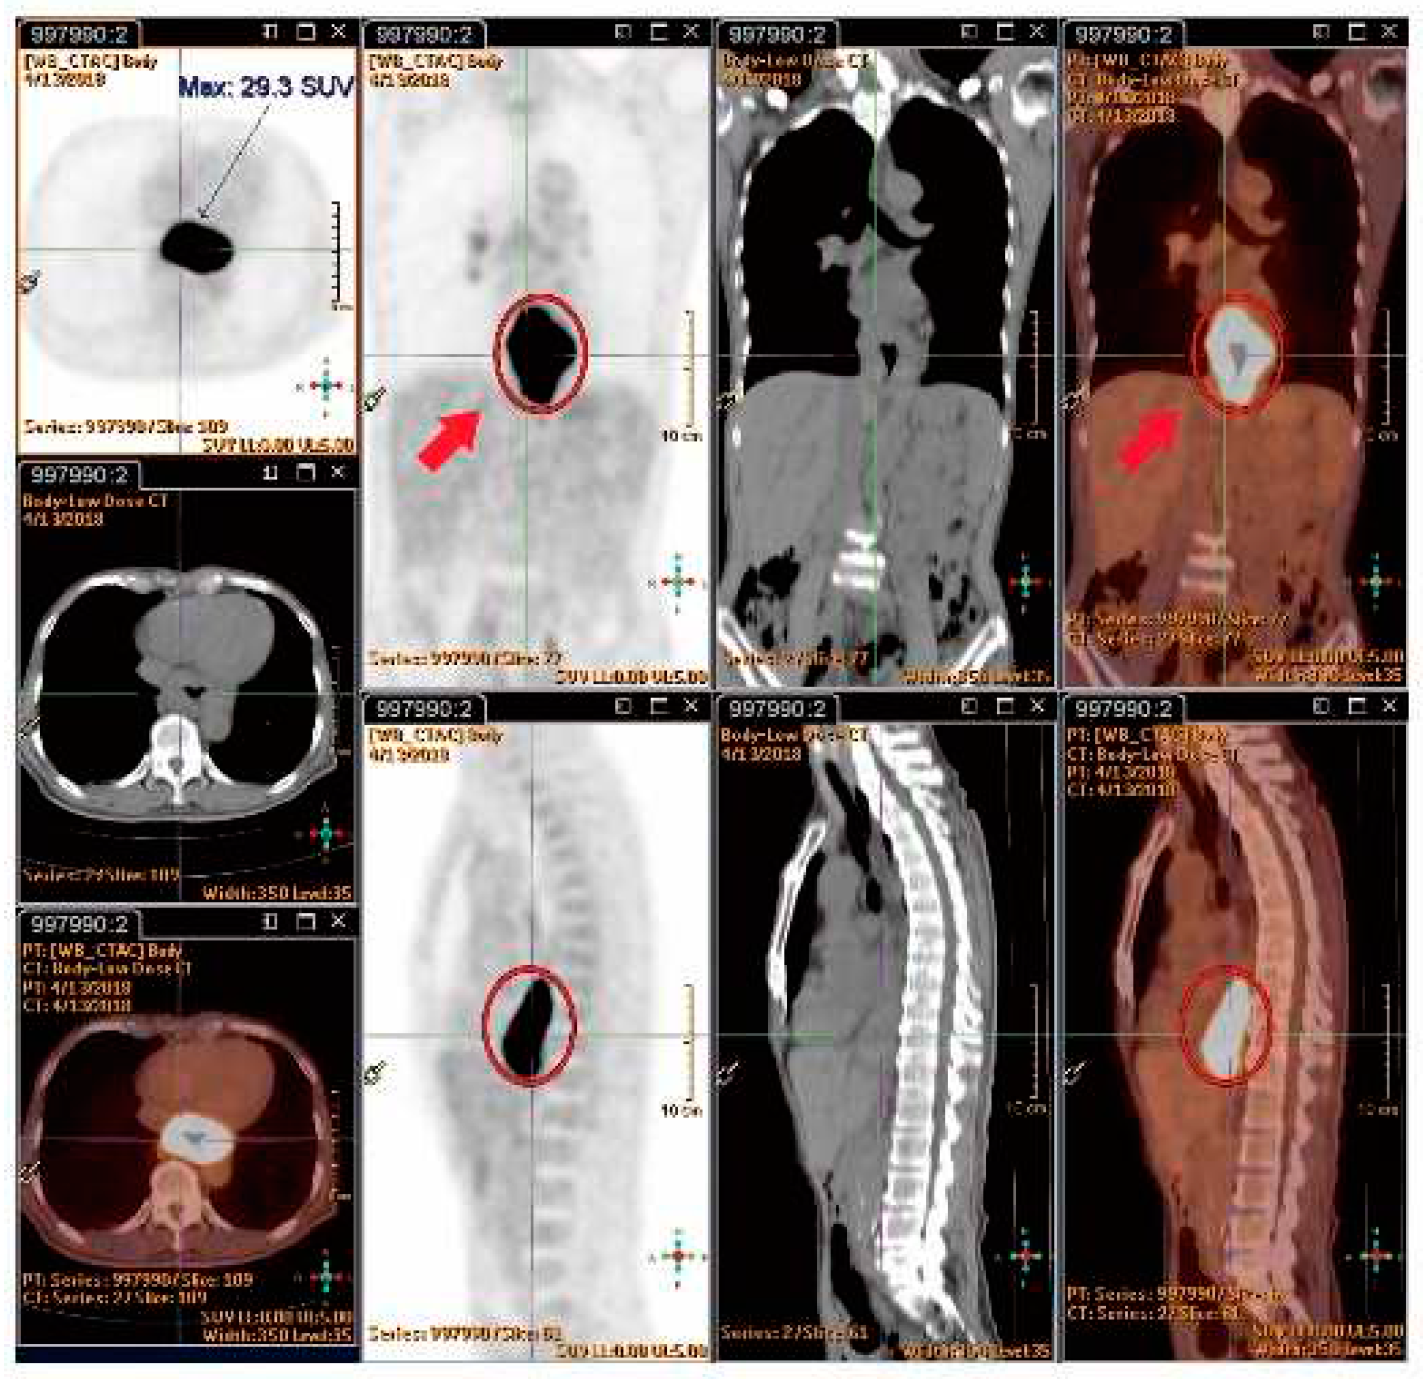

4.7.4. SUVmax value of PET/CT Serve as Indicator of RILD?